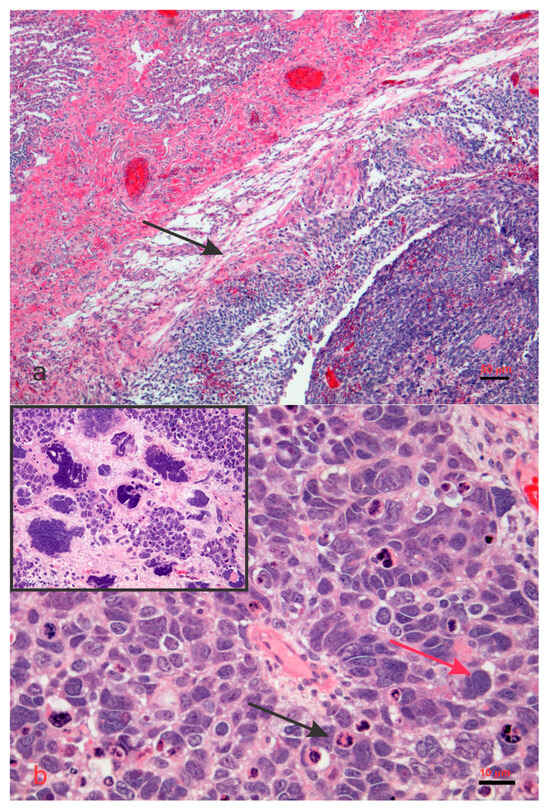

- Hill, D.A.; Ivanovich, J.; Priest, J.R.; Gurnett, C.A.; Dehner, L.P.; Desruisseau, D.; Jarzembowski, J.A.; Wikenheiser-Brokamp, K.A.; Suarez, B.K.; Whelan, A.J.; et al. DICER1 mutations in familial pleuropulmonary blastoma. Science 2009, 325, 965. [Google Scholar] [CrossRef]

- Seki, M.; Yoshida, K.; Shiraishi, Y.; Shimamura, T.; Sato, Y.; Nishimura, R.; Okuno, Y.; Chiba, K.; Tanaka, H.; Kato, K.; et al. Biallelic DICER1 mutations in sporadic pleuropulmonary blastoma. Cancer Res. 2014, 74, 2742–2749. [Google Scholar] [CrossRef] [PubMed]

- Fernández-Martínez, L.; Villegas, J.A.; Santamaría, Í.; Pitiot, A.S.; Alvarado, M.G.; Fernández, S.; Torres, H.; Paredes, Á.; Blay, P.; Balbín, M. Identification of somatic and germ-line DICER1 mutations in pleuropulmonary blastoma, cystic nephroma and rhabdomyosarcoma tumors within a DICER1 syndrome pedigree. BMC Cancer 2017, 17, 146. [Google Scholar] [CrossRef] [PubMed]

- Brenneman, M.; Field, A.; Yang, J.; Williams, G.; Doros, L.; Rossi, C.; Schultz, K.A.; Rosenberg, A.; Ivanovich, J.; Turner, J.; et al. Temporal order of RNase IIIb and loss-of-function mutations during development determines phenotype in pleuropulmonary blastoma/DICER1 syndrome: A unique variant of the two-hit tumor suppression model. F1000Research 2015, 4, 214. [Google Scholar] [CrossRef] [PubMed]